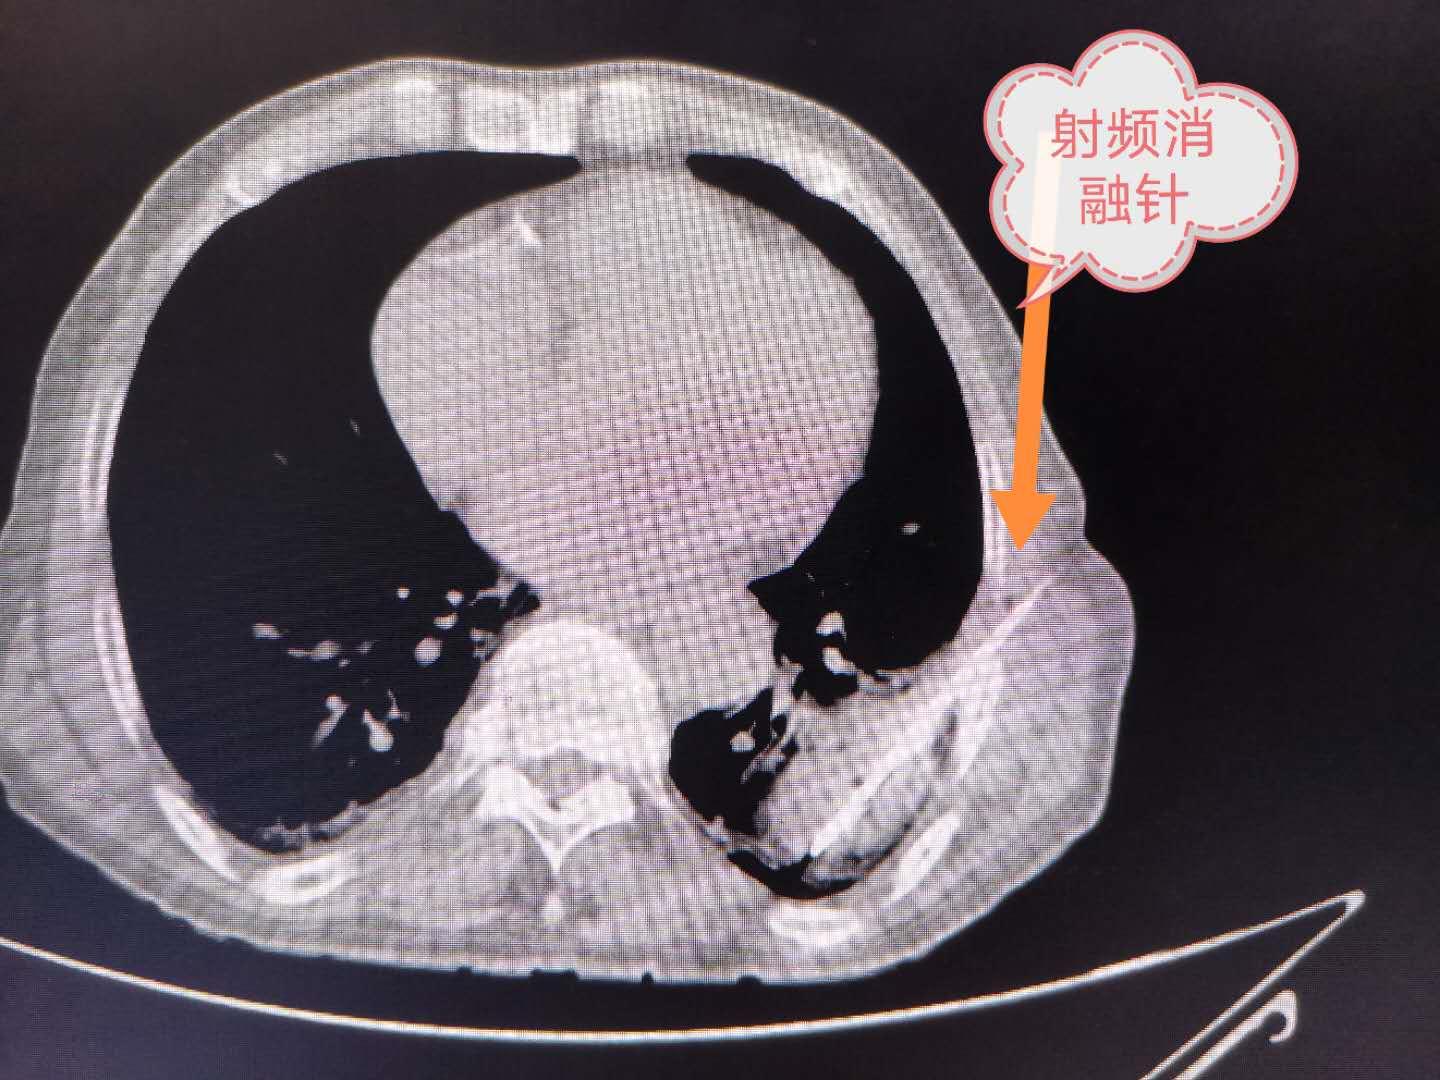

介入手术中

CT引导下射频针插入肿瘤内,发射频波,把肿瘤加热到100摄氏度

简单的术前准备后,也就是查一下传染病四项,肝肾功能以及出凝血时间等,老爷子躺在CT室检查床上,CT扫描定位准确并设定好穿刺途径后,消毒铺手术巾,局部打了一点点*醉药麻**(麻醉师候着,如果疼的厉害了就麻翻),用一根细细的穿刺针向肿瘤穿刺,到位后先取了一点病变组织用来做病理检查,并做肿瘤基因检测,看看有没有合适的靶向治疗药物可以选择。然后接上射频发射仪把肿瘤加热到100摄氏度,十分钟后,在老爷子刚刚感觉有点疼的时候,手术结束。回到病房,又用了一点止疼药,输了一次抗生素,第二天,基本上没有啥不舒服的感身体还算可以。当天下午就办理了出院手续回家(我们医院隔壁家属院)继续观察了。